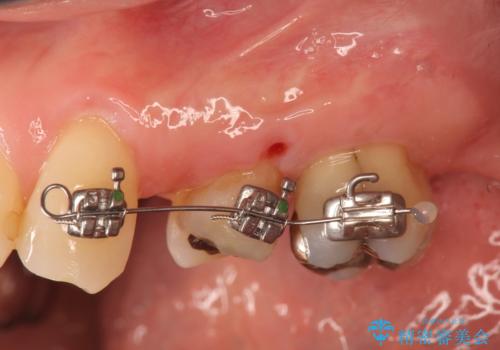

ブリッジの長期的な予後のためには支台となる歯の位置・清掃性が重要となりますが、今回ブリッジを製作するにあたり位置の悪い左上小臼歯を補綴前小矯正を行い位置を改善します。

補綴前小矯正について

矯正を行うことで歯を適切な位置に動かすことでより、清掃性に優れ長期的な予後を見込むことのできるブリッジを製作することができました。